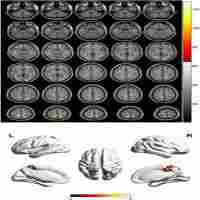

| Abstract | There is a noticeable lack of systematic researches on evaluating the correlation between serum estrogen levels and changes in brain functional areas of perimenopausal women.The aim of this study is to investigate the regional spontaneous brain activity changes in perimenopausal women. Based on the resting-state functional magnetic resonance imaging datasets acquired from 25 perimenopausal women and 20 healthy women of reproductive age, a two-sample t-test was performed on individual normalized regional homogeneity (ReHo) maps. Relationships between abnormal ReHo values and the self-rating anxiety scale (SAS), the self-rating depression scale (SDS) were investigated with Pearson correlation analysis. We also investigated the correlation between abnormal ReHo values and serum estrogen level. In the perimenopausal group, we found increased ReHo in the right posterior cerebellum (region 2), left middle frontal gyrus and left middle cingulate gyrus ( $P<0.05$ ). Additionally, the ReHo values in left middle frontal gyrus and leftt middle cingulate gyrus showed positively significant correlation with the SAS, SDS scores. On the contrary, there was no significant correlation between the ReHo value in right posterior cerebellum and SDS, SAS scores. In the perimenopausal group, the ReHo values in the left middle frontal gyrus and left middle cingulate gyrus were negatively correlated with the serum estrogen level ( $P<0.05$ ). The results of this preliminary study have suggested that abnormal spontaneous activities of multiple brain regions during resting state was already altered in perimenopausal women. Alterative activities might be related to emotional regulation deficits and cognitive impairment, and might potentially represent the neural mechanism underlying perimenopausal period. |